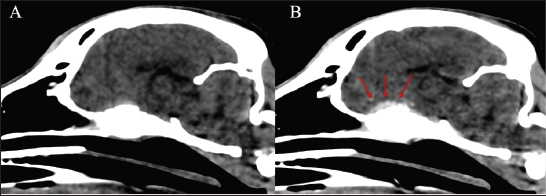

The dog received general anesthesia and underwent a computed tomography scan of the head and cervical vertebral column before and after iodinated intravenous contrast injection with iohexol at 400 mg/kg (Omnipaque, General Electrics Healthcare, Cork, Ireland). Anesthesia was induced with propofol (Propomitor, Orion Pharma, Madrid, Spain) at 4 mg/kg IV and was maintained with 1.5% isoflurane (Isofane, Piramal Critical Care B.V., Voorschoten, Netherlands) in oxygen under controlled ventilation. A 16-slice helical CT scanner (Brivo CT385, General Electrics Healthcare, Madrid, Spain) was used for imaging acquisition. The images revealed an aggressive polyostotic, osteolytic, and osteoproliferative lesion with periosteal reaction affecting the basisphenoid and presphenoid bones and, therefore, compromising the optic canal and orbital fissure (Fig. 1). The lesion extended intracranially at the level of the rostral and middle cranial fossa as an isoattenuating, ill-defined extra-axial space-occupying mass with marked and homogenous contrast enhancement (Fig. 2). No abnormalities were found in the cervical column images. A cisternal cerebrospinal fluid tap was performed, and the sample was analysed, the results of which were within the reference ranges. Polymerase chain reaction in the cerebrospinal fluid was not performed as the total nucleated cell count was within normal limits.

Fig. 2. Soft tissue window sagittal reconstruction of the head (A) pre-contrast and (B) post-contrast administration, showing the contrast-enhancing extra-axial lesion affecting the sphenoid bone (red arrows).